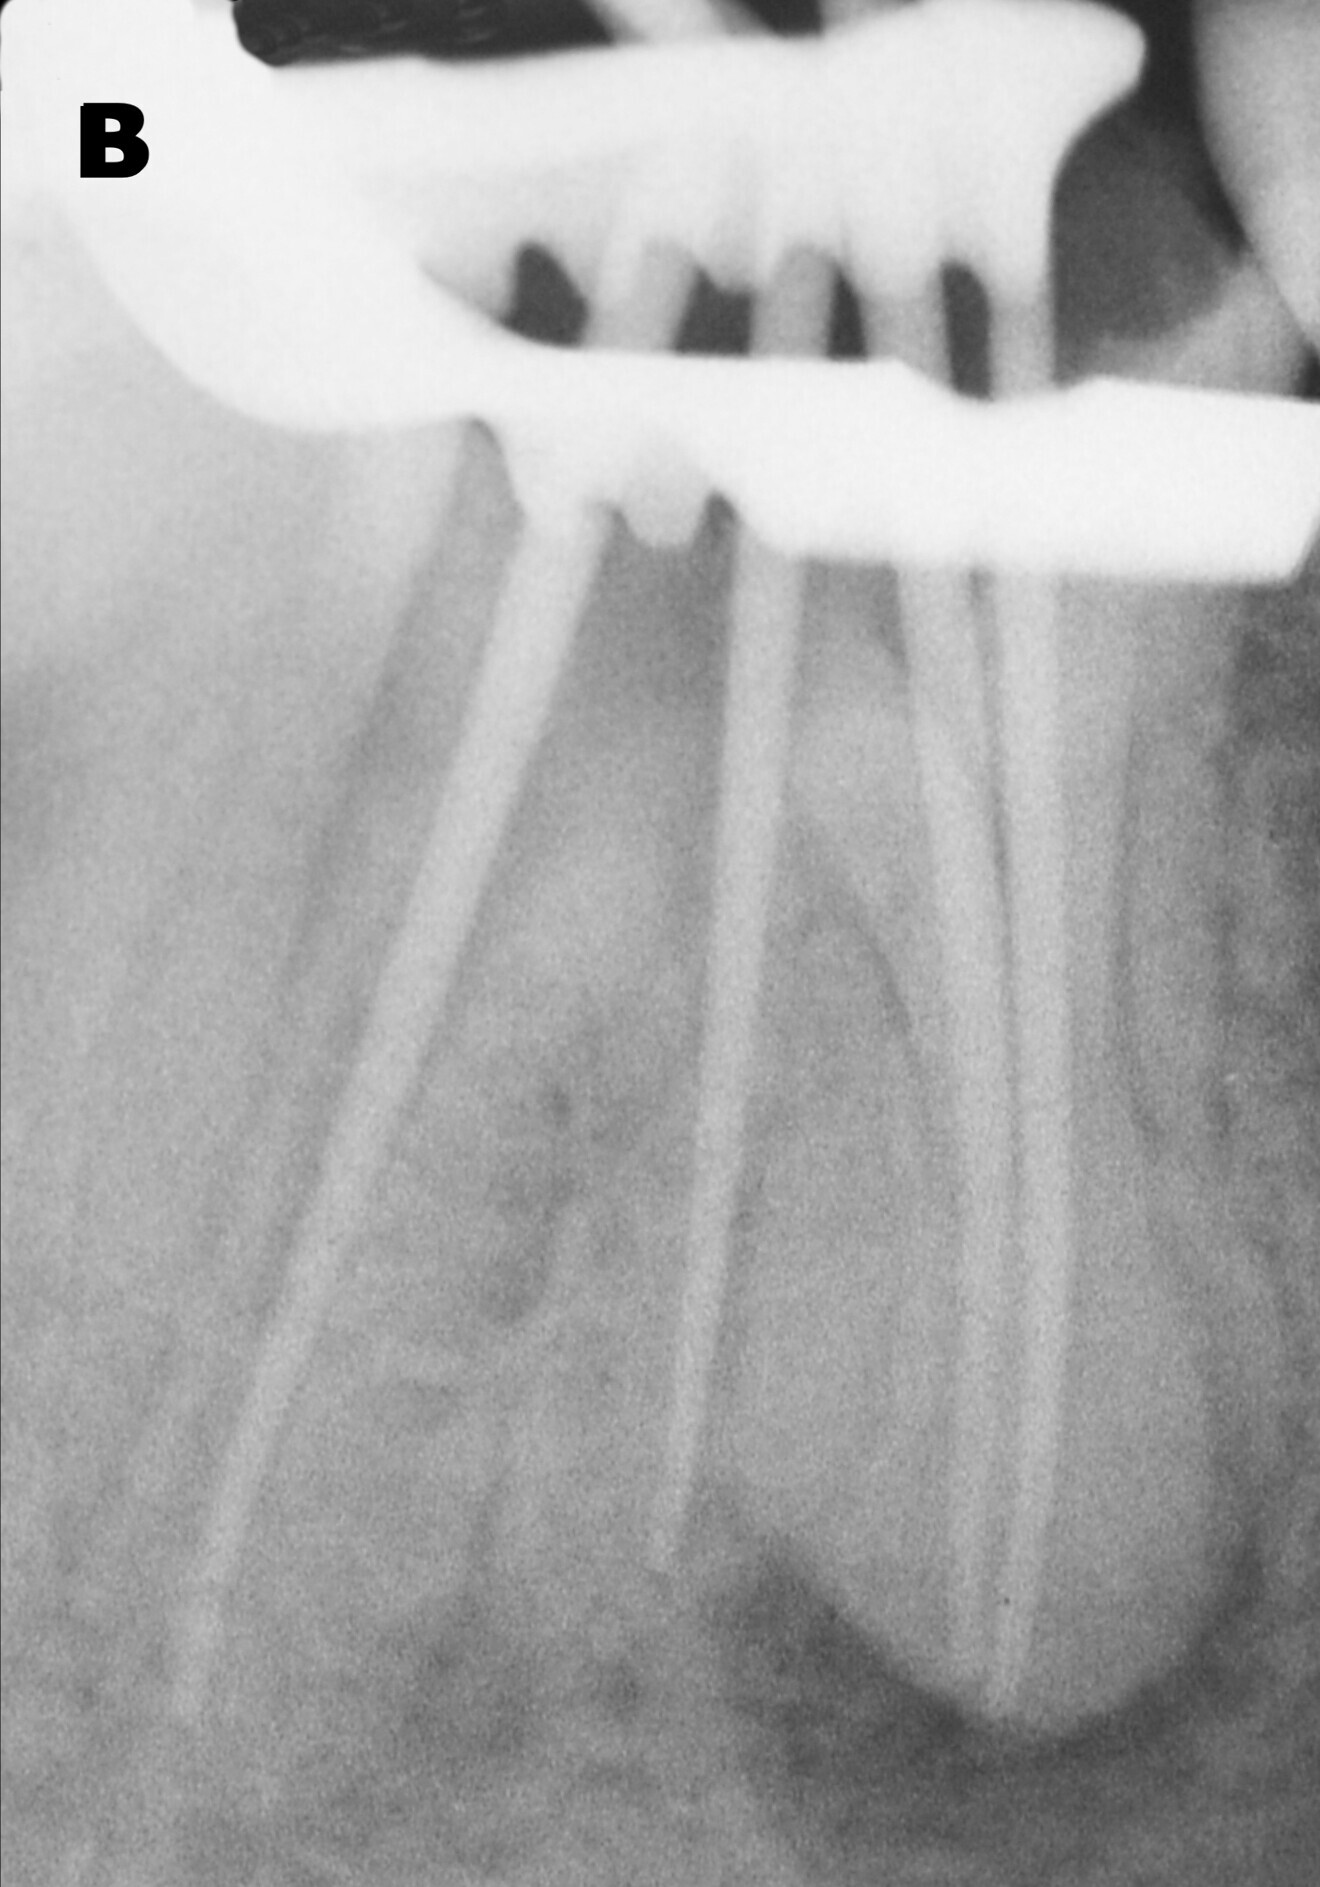

The first step was the endodontic reintervention. After local anaesthesia, the operative field was isolated with a dental dam, and a dental dam clamp was placed around tooth #46. The old amalgam was removed, taking care to preserve sound tissue. Once the endodontic filling had been reached, remnants of amalgam and cement were carefully removed. The endodontic filling was removed with rotary instruments for canal shaping and retreatment (ProTaper Universal retreatment files, Dentsply Sirona). The coronal third was treated with the D1 file (30/0.09), the medium third with the D2 file (25/0.08) and the apical third with the D3 file (20/0.07). An entirely mechanical removal procedure was performed to avoid the use of endodontic solvents. The non-treated root canal in the distal root was located and manually prepared with size 15, 20 and 25 K-files. The same files were used for the radiographic check of the working length, which was measured with an apex locator (Fig. 2a).

ProTaper Next Conform Fit gutta-percha points (Dentsply Sirona), matched to the size of the canals prepared with ProTaper Next files, were inserted in each root canal and checked with an intra-oral radiograph (Fig. 2b). The root canals were then filled by means of a lateral condensation technique with cold gutta-percha and manual spreaders. Accessory gutta-percha points and an endodontic sealer (ADSEAL, Meta Biomed) were used as well.

Once completed, the gutta-percha points were cut manually with a hot instrument. After cleaning the dentine surface of the pulp chamber floor, a radiographic control was carried out (Fig. 3). The results were promising. The radiograph showed properly prepared, well-filled root canals, including the canal in the critical distal root. In all four root canals, the working and filling lengths were now well established.

Figs. 23a & b: Radiographs before (a) and after (b) treatment, showing dramatic differences. The endodontic treatment had been corrected and the restoration was well adapted and shaped. The interproximal relationships had been re-established through the anatomy of the endocrown. There were no gaps between the restoration and the endodontic filling. The sealing of the endodontic treatment was complete and tight.

The endodontic retreatment and endocrown restoration of a badly damaged molar were carried out in a single clinical session. Postoperative clinical photographs and radiographs verified the results of the treatment: the molar recovered its anatomical forms and thus its function.

The endocrown restoration and the build-up material occupied the enlarged pulp chamber completely; the access to the root canals was thus closed hermetically. The margins of the endocrown also showed an adequate seal. The tight seal of the restoration will play a crucial role in the long-term results of the endodontic treatment.

Regarding the endodontic retreatment, the preparation and seal of the root canals were appropriate, a suitable 3D seal was achieved and the working length was corrected. Also, the previously untreated root canal in the distal root was properly prepared and sealed (Fig. 23).